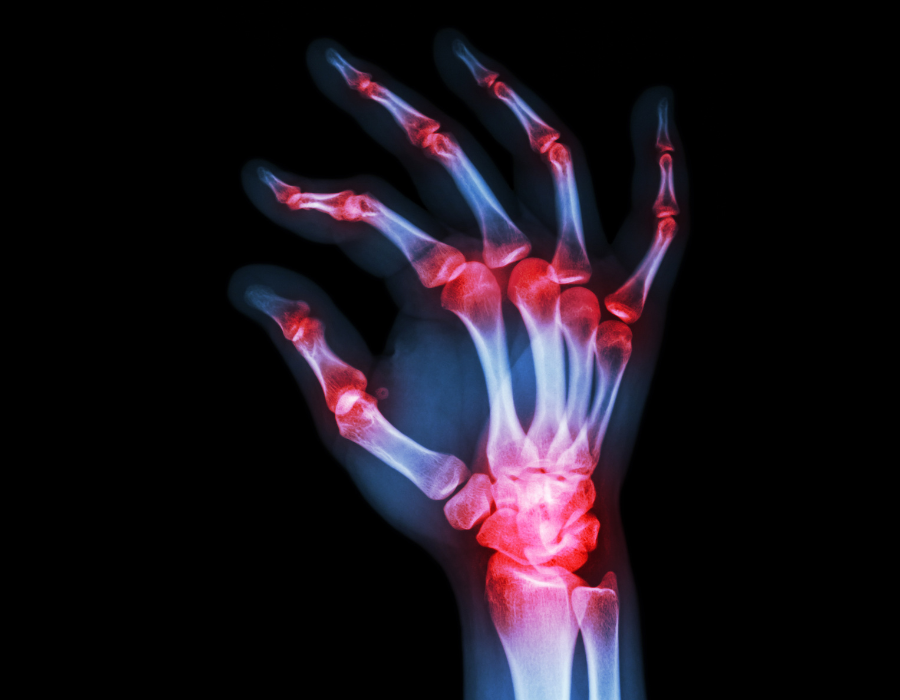

Viêm khớp nhiễm khuẩn hay là tình trạng nhiễm trùng bên trong khớp do vi khuẩn xâm nhập nội khớp, gây ra tình trạng sưng tấy và đau khớp. Viêm khớp nhiễm khuẩn rất ít khi xuất hiện cùng lúc ở nhiều khớp. Tình trạng nhiễm trùng có thể xảy ra do vi trùng di chuyển qua dòng máu từ một bộ phận khác của cơ thể.

Tình trạng nhiễm trùng ở khớp cũng có khả năng đến từ một chấn thương xuyên khớp mang vi trùng trực tiếp đi vào khớp. Các khớp thường dễ bị nhiễm trùng là khớp gối, khớp háng, khớp cổ tay, khuỷu tay, khớp vai và khớp mắt cá chân.

Các khớp bị viêm sẽ sưng và đỏ

Xuất hiện tình trạng ấm, nóng tại vị trí khớp bị viêm

Chẩn đoán hình ảnh: Chụp X-quang cùng những kỹ thuật chẩn đoán hình khác đối với khớp bị viêm sẽ hỗ trợ đánh giá tình trạng bệnh chuẩn xác.